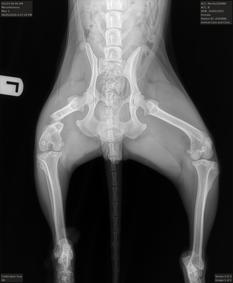

Myrtle from @NYCACC x-rays show that the left femur has a displaced mid-diaphyseal fracture. Based on the radiographs it's suspected that this fracture is at least several weeks old to possibly months old, and she needs orthopedic surgery. This is going to be very costly... If

8

168

121